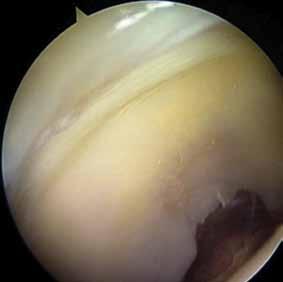

Fråga 2012-6 5p

Kvinna 57 årig tidigare frisk kvinna som inte tidigare har haft några problem med sina knäleder. En dag under vårens trädgårdsarbete känt smärtor i vänster knäled. Söker efter några dagar som jourfall då smärtorna snarast tenderar att öka. I status finner du lätt hydrops. Lätt rörelseinskränkning vänster jämfört med höger knäled. Lätt till måttlig ömhet medialt. Normal SR och CRP.

a. Differentialdiagnoser? (1p)

b. Hur handlägger Du patienten vid detta besök? (2p)

c. Hur utreder man ytterligare om patienten återkommer pga tilltagande besvär efter ett par veckor? (2p)

a. Troliga diagnoser är degenerativ meniskruptur/artros, spontan knäledsosteonekros eller insufficiensfraktur.

b. Noggrant knä- och höftstatus eventuellt slätröntgen och patientinformation om möjliga diagnoser. Smärtlindring och aktivitetsråd.

c. Vidare utredning med MR kan vara

indicerad speciellt för att kartlägga en eventuell osteonekros. Tc-scintigrafi kan också leda till rätt diagnos.